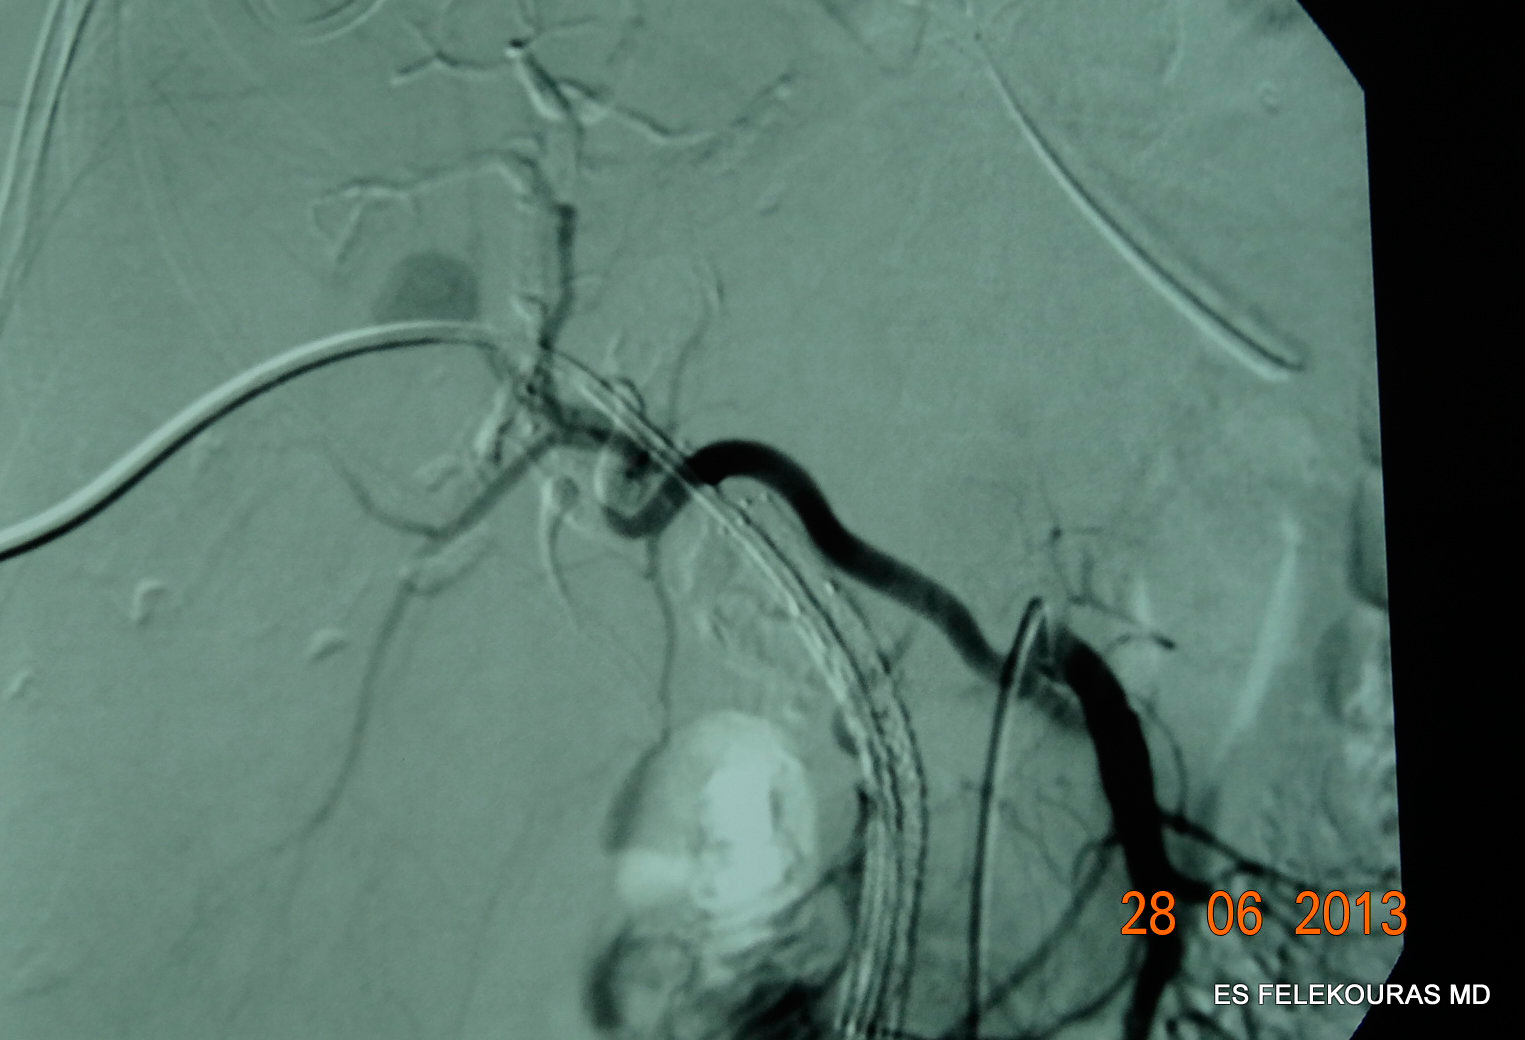

Επί υποψίας αιμοχολίας, η πρώτη εξέταση που θα πρέπει να διενεργηθεί είναι η ενδοσκόπηση του ανώτερου πεπτικού, ώστε να αποκλεισθεί άλλη αιτία αιμορραγίας, ενώ ταυτόχρονα μπορεί να είναι ορατή η αιμορραγία από το φύμα του Vater. Η ενδοσκόπηση του ανώτερου πεπτικού είναι διαγνωστική για αιμοχολία μόνο στο 10% των περιπτώσεων (εικόνα 1). Επί θετικής ενδοσκόπησης και σχεδιασμό για συντηρητική αντιμετώπιση του ασθενούς, δεν χρειάζεται περαιτέρω έλεγχος. Το υπερηχογράφημα και η αξονική τομογραφία μπορεί να αναδείξουν ενδοηπατικό όγκο ή αιμάτωμα. Ενεργός αιμορραγία μπορεί να γίνει ορατή, με τη βοήθεια ΑΤ με ενδοφλέβιο σκιαγραφικό με τη μορφή λιμνάζοντος σκιαγραφικού, ενδοαυλικών θρόμβων στα χοληφόρα καθώς και διάταση αυτών. Η ΑΤ ενδέχεται να αποκαλύψει, επίσης, παράγοντες κινδύνου οι οποίοι σχετίζονται με την αιμοχολία, όπως κυστικές κεντρικές βλάβες και ανευρύσματα.

Εικόνα 1: Εικόνα αιμοχολίας σε ERCP μετά από παροχέτευση ηπατικού αποστήματος (βλ. καθετήρα).